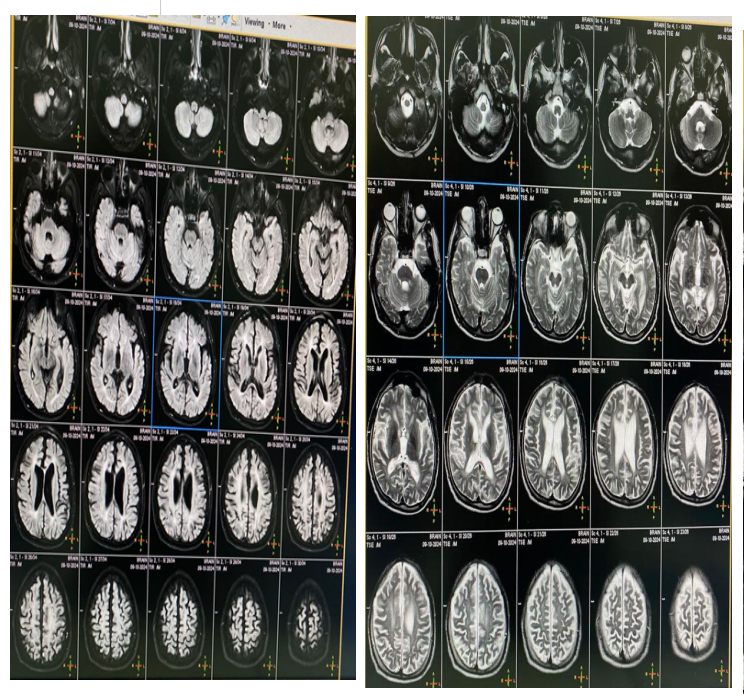

Investigations. Vitamin E 9.87, HbA1c 5. Serum lactate 12.43, pyruvate 0.36. MRI brain showed Symmetric ventricular dilation and cortical atrophy.MRI cervical was normal (Figure 1).IQ of 64 (Figure 2). EEG showed bilateral focal epileptogenic activity (Figure 3). Nerve conduction studies and electromyography indicated severe axonal sensorimotor polyneuropathy worsened compared to previous studies (Figure 4).

Cortical atrophy